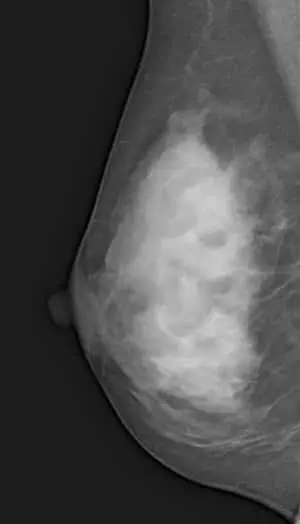

日本人を含むアジア人女性では、欧米人と比較してマンモグラフィーでがんが隠れやすい、デンスブレストの方の割合が多いとされています。50歳以下では80%近くが高濃度・不均一高濃度であるという報告があります。

放射線学分野で最も権威の高い科学雑誌「Radiology」では、透き通っている乳房(高年齢の方)と、白く曇っているデンスブレスト(多くの働く年齢の女性)ではがんの発見率が2倍も違うことが分かっています。

DWIBS(ドゥイブス)検査ではマンモグラフィーと違い、乳腺の濃度の影響をほとんど受けないため、デンスブレストの方でも問題なく受けていただけます。

A日本人女性の多くは、乳腺の濃度が高いデンスブレスト(高濃度乳房)だといわれています。デンスブレストはマンモグラフィーだと白く濁り、がんと見分けがつかなくなってしまいます。しかし、MRIを駆使した乳房DWIBSはデンスブレストの影響を受けず、がんを黒く映し出すため、日本人をはじめアジア人女性に適した乳がん検診です。